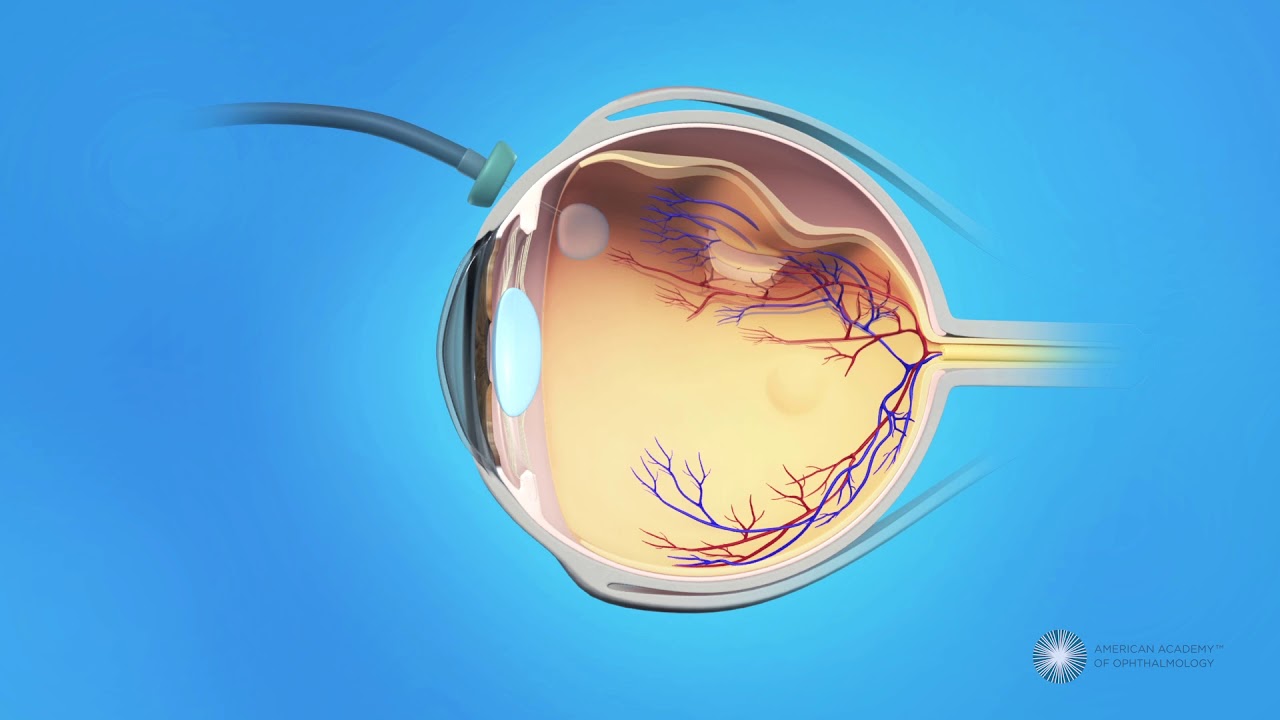

Vitrectomy Surgery For Detached Retina YouTube

https://i.ytimg.com/vi/yDACxM-yM1w/maxresdefault.jpg

Vitrectomy Fraser Eye Care Center